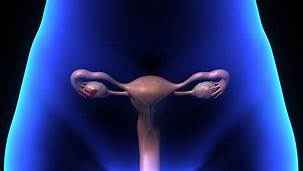

El síndromes de ovarios poliquísticos es un trastorno hormonal común entre las mujeres en edad reproductiva. Las mujeres con síndrome de ovario poliquístico pueden tener periodos menstruales prolongados